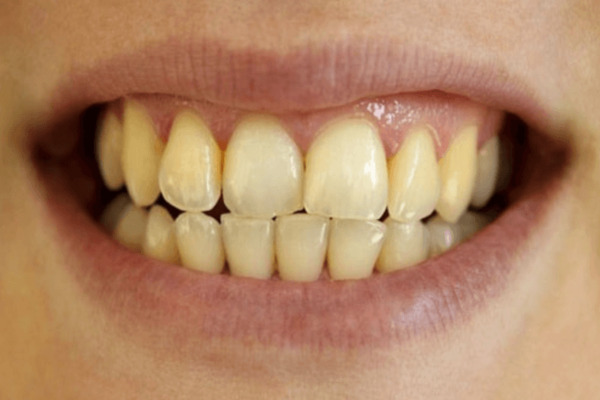

Răng đổi màu: vàng, nâu, xỉn, mất độ bóng

Thay đổi màu răng là dấu hiệu dễ thấy khi men răng bị tổn thương hoặc mòn mỏng. Răng có thể ngả vàng, nâu hoặc xỉn màu do mất khoáng, mảng bám tích tụ hoặc các vết ố lâu ngày. Khi men răng mất độ bóng tự nhiên, lớp ngà bên trong lộ ra nhiều hơn, làm răng trông kém thẩm mỹ và khiến người bệnh mất tự tin.

Tình trạng đổi màu này còn liên quan đến thói quen ăn uống, hút thuốc hoặc vệ sinh răng miệng chưa đúng cách. Việc điều trị sớm như tẩy trắng răng, lấy cao răng hoặc phục hình sứ có thể giúp cải thiện đáng kể, phục hồi lại sự sáng đẹp và bảo vệ răng tốt hơn trong thời gian dài.

Bề mặt răng mòn, lộ lớp ngà vàng

Khi men răng bị mòn đi, lớp ngà màu vàng bên trong sẽ lộ ra, khiến răng trông xỉn màu, thô và kém mịn hơn. Vì ngà mềm và nhạy cảm hơn men, răng dễ bị kích thích khi gặp đồ ăn nóng, lạnh hoặc có axit. Tình trạng này không chỉ ảnh hưởng đến thẩm mỹ, đặc biệt ở răng cửa, mà còn gây ê buốt khi ăn uống.

Để cải thiện, bạn cần chăm sóc răng đúng cách, tránh các tác nhân gây mòn men và dùng các sản phẩm giúp bảo vệ men răng. Trong trường hợp cần thiết, trám hoặc bọc sứ sẽ giúp phục hồi bề mặt răng và giữ cho hàm răng luôn khỏe đẹp. Các phương pháp này hỗ trợ bảo vệ ngà răng, giúp duy trì sức khỏe răng miệng lâu dài.